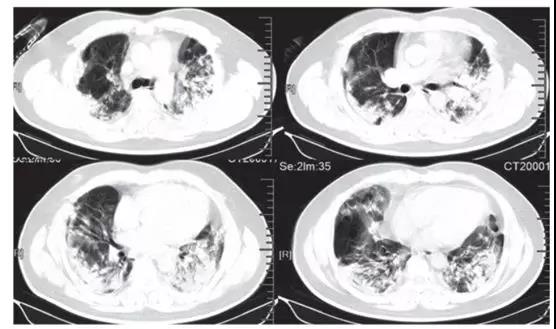

中国学者Lancet刊文称新型病毒感染有四大常见表现: 发烧、干咳、呼吸困难和双侧毛玻璃状样变!